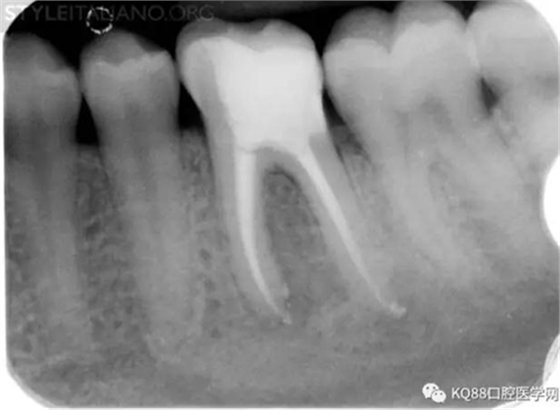

Img. 4 - Case 2: This necrotic first mandibular molar was treated in one visit, and the patient complained of post-operative pain. Analgesics and antibiotics were prescribed, and occlusion relieved. Symptoms disappeared after two days, and a radiographic follow-up after two years showed healing of the periradicular lesion.